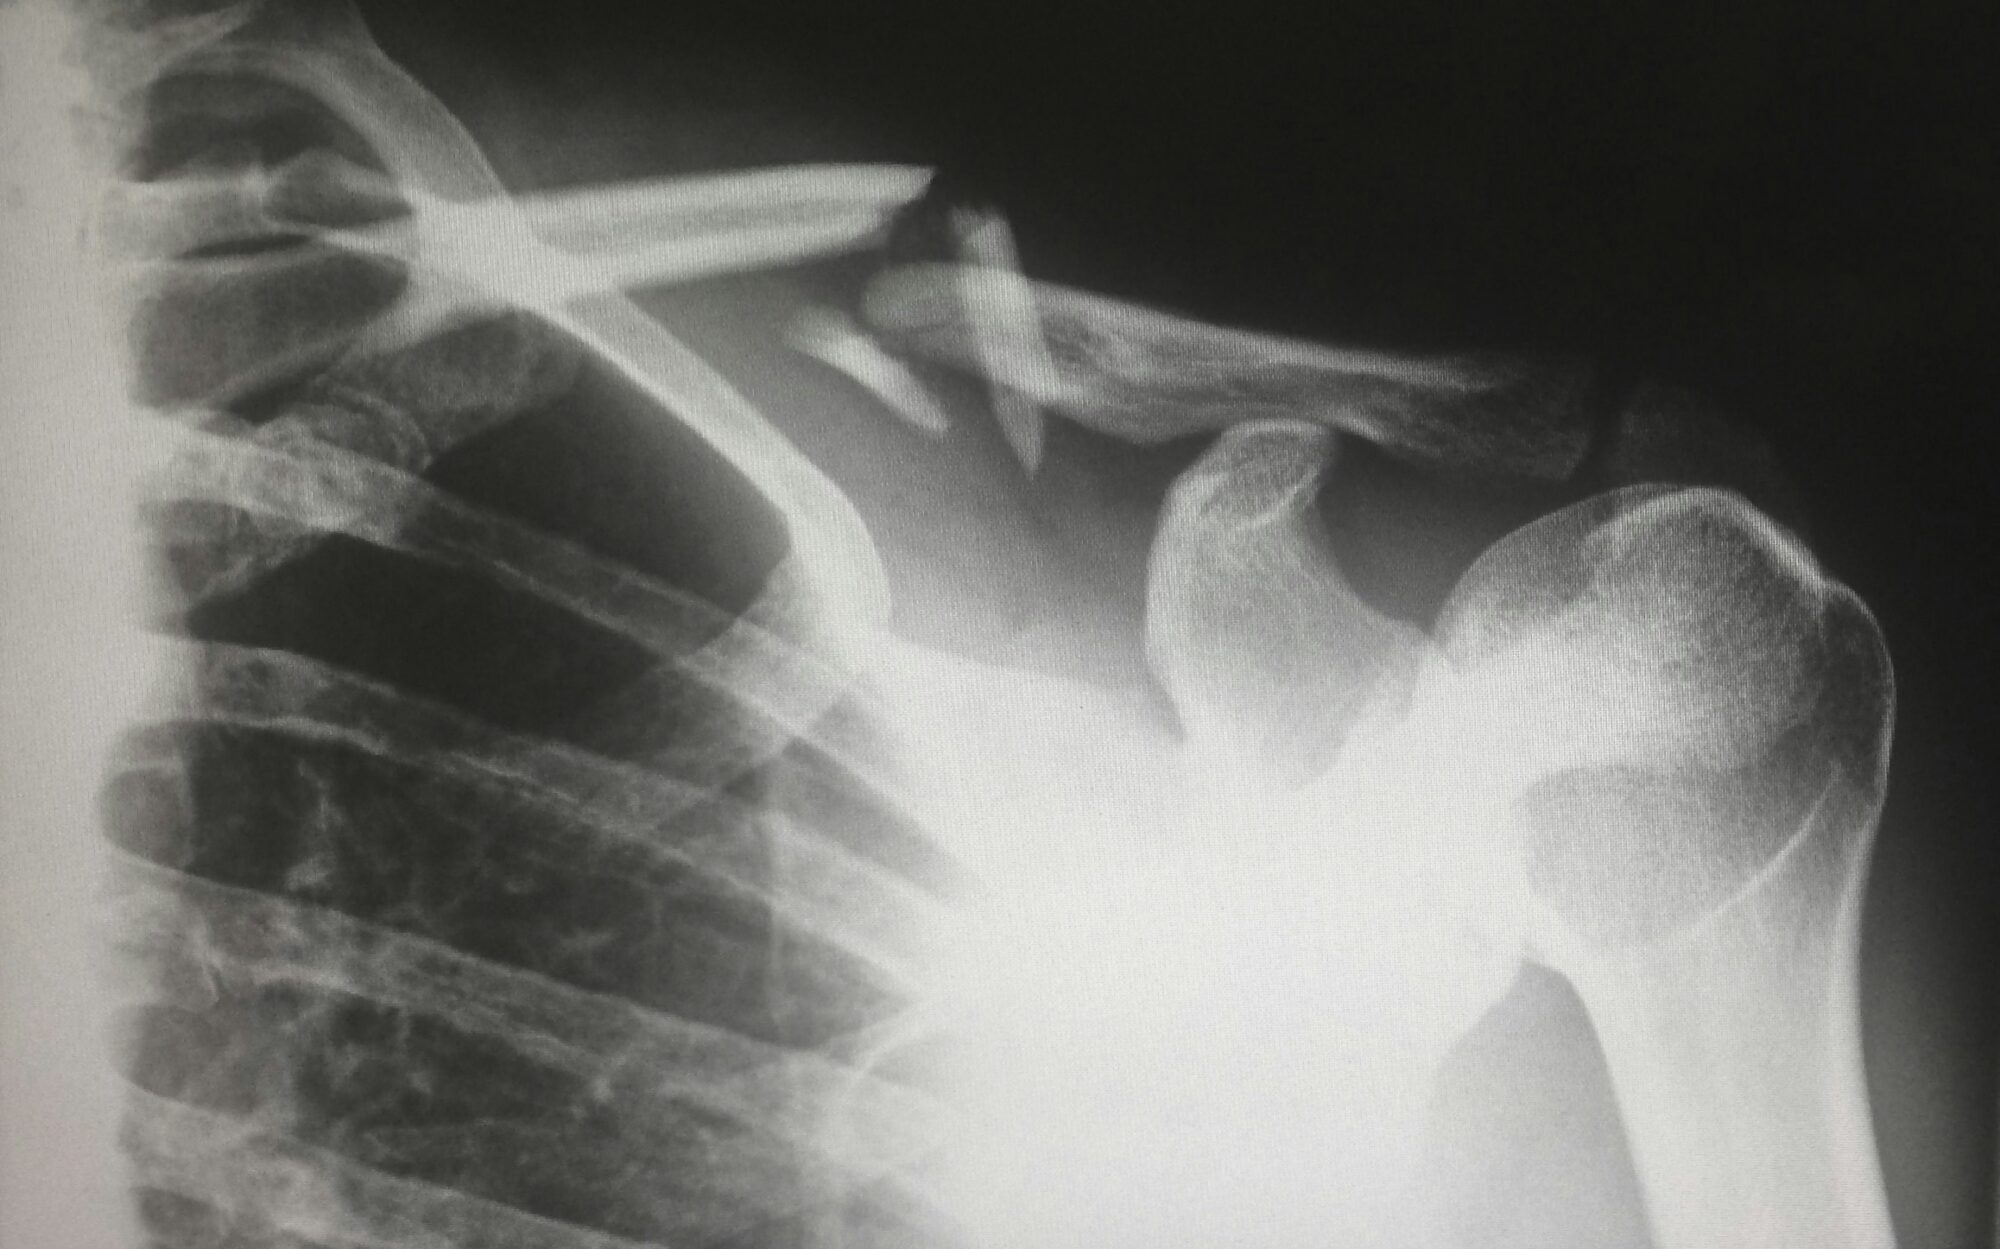

- Обследование и диагностика травм и повреждений опорно-двигательной системы.

- Использование методов консервативного лечения, таких как фиксация переломов и вывихов, шинирование и гипсование.